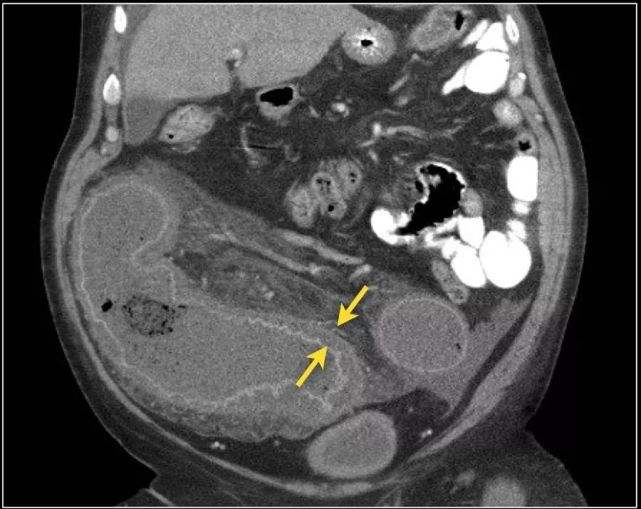

CT虽然不是诊断肠梗阻的主要方法,但有时有助于病因的诊断。肠梗阻时CT可显示扩张的肠曲,并可见多个肠腔内气-液平面、肠壁增厚以及直径增大。如果肠管互相融合成团,或与腹壁相连,提示为粘连性肠梗阻。如有肠套叠,则可显示出典型CT征象,出现三层肠壁征。患者还可出现腹痛、呕吐、腹胀等症状。